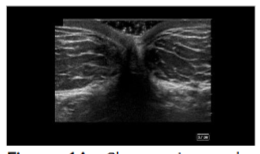

The layers of the abdomen can be evaluated from superficial to deep: the epidermis and dermis appear thin and hyperechoic; the adipose layer presents as hypoechoic and lobular with hyperechoic fibrous septa. Deep to the adipose layer, muscle appears relatively hypoechoic, separated by fine hyperechoic perimysium, while the bowel wall appears relatively hyperechoic with a hypoechoic lumen and is easily identified by its movement while the patient is at rest.

Cadavers were positioned supine. A global ultrasound scan was performed, starting at the umbilicus in short axis to the rectus abdominis, extending laterally to visualize the external and internal oblique muscles and their fascial junctions. The dermis, adipose layer, muscle layers, and bowel were identified to demarcate a safe adipose harvest zone.

The apical, mantle, and deep layers of the subcutaneous adipose compartment were distinguished, with the mantle and deep layers selected as preferred harvest targets due to their greater thickness. Depth markers on the ultrasound screen were used to measure adipose thickness and define the field size. Areas with potential umbilical hernias or fascial defects were identified and avoided. In clinical practice, Color Doppler can be employed to exclude vascular structures; however, it was not utilized in this cadaveric study.